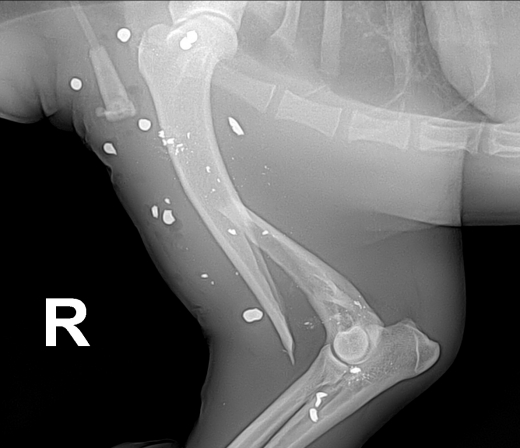

작은 몸에 스무 발 이상 박힌 ‘전신 총상’

처음 마주한 개의 상태는 처참함 그 자체였다. 개는 차가운 뜬장에 죽지 못해 살아있는 듯한 모습으로 누워 있었다. 케어는 서울 소재 대형 동물병원으로 급히 개를 이송했다. 검진 결과, 온 몸에 산탄이 박혀 있었다. 일부 총탄은 깨져서 파편으로 몸 구석구석 박혀 있는 상황이었다. 신경계까지 건드린 끔찍한 총상이었다. 이 작은 개와, ‘전신 총상’이라는 검사결과는 너무나도 어울리지 않아 보였다. 게다가 질염을 포함해 심장사상충, 골절상까지. 온 몸이 성한 데가 없었다.